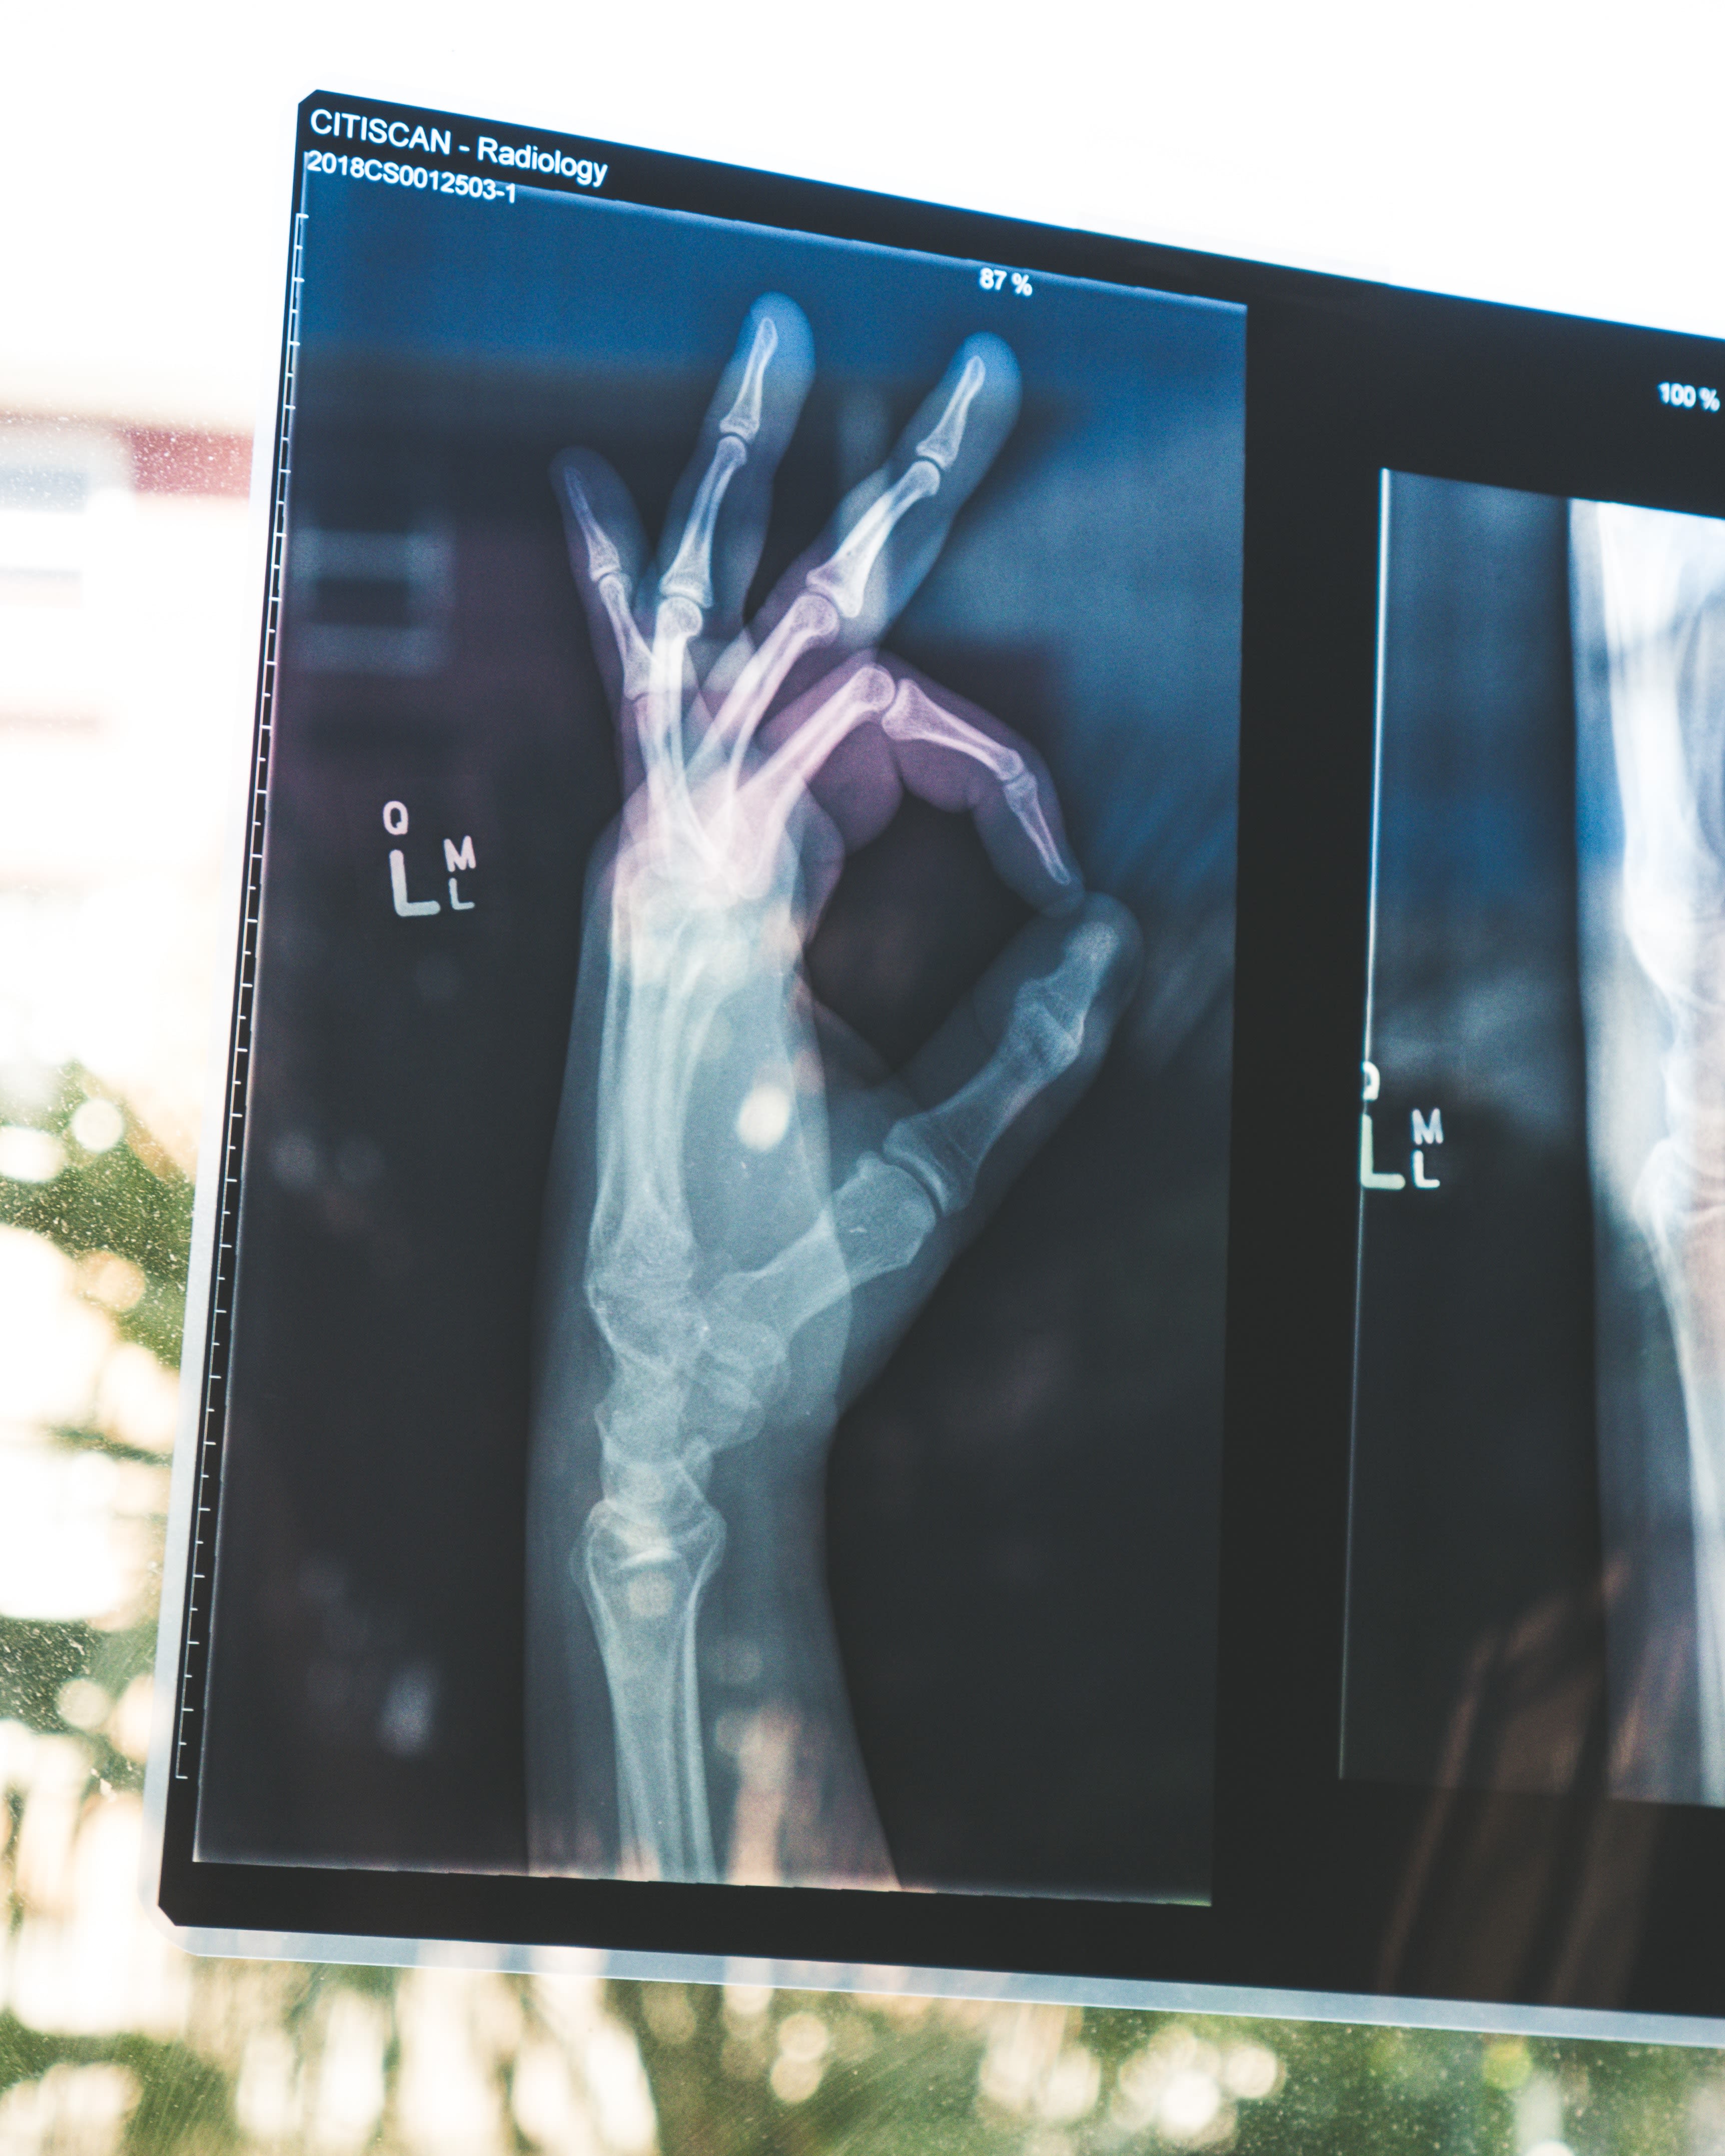

AI and ML are transforming healthcare by enabling more accurate diagnoses, personalised treatments, and efficient administrative processes. Algorithms can analyse medical images faster and more accurately than human doctors, leading to earlier detection of conditions like cancer. Personalised medicine, powered by ML, tailors treatments to individual genetic profiles, enhancing effectiveness and reducing side effects. Additionally, AI-driven administrative tools streamline scheduling, billing, and patient record management, freeing up healthcare professionals to focus more on patient care.